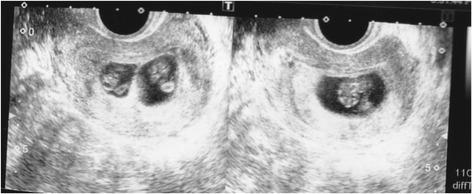

We describe two cases of dichorionic triplet pregnancy after a frozen-thawed poor-stage embryo transfer. A 39-year-old and a 41-year-old woman underwent ART treatment. The first patient underwent intracytoplasmic sperm injection (ICSI) at 34 years of age, and two frozen-thawed poor-stage embryos were transferred at 39 years of age with assisted hatching, resulting in a trichorionic triamniotic triplet pregnancy. The second patient underwent ICSI, and two poor-grade blastocysts were transferred followed by assisted hatching, resulting in a dichorionic triamniotic triplet pregnancy. In the first case, the heartbeat of one monozygotic twin fetus had stopped on day 48 post-transfer (9 weeks 2 days), resulting in a dichorionic diamniotic twin pregnancy. A healthy boy and girl were delivered by elective caesarean section at 36 weeks, 5-days gestation. In the second case, the patient underwent selective reduction of the monochorionic twins, resulting in a single pregnancy that was vaginally delivered without any problems at 38 weeks 0-days gestation.

我们描述了两例冻融低质量胚胎移植后双绒毛膜三胎妊娠的病例。一名39岁和一名41岁的女性接受了辅助生殖技术治疗。第一名患者34岁时接受了卵胞浆内单精子注射(ICSI),39岁时移植了两枚冻融低质量胚胎并进行了辅助孵化,结果是三绒毛膜三羊膜囊三胎妊娠。第二名患者接受了ICSI,随后移植了两枚低质量囊胚并进行了辅助孵化,结果是双绒毛膜三羊膜囊三胎妊娠。在第一例中,一个单卵双胎胎儿的心跳在移植后第48天(9周2天)停止,导致双绒毛膜双羊膜囊双胎妊娠。在妊娠36周5天时通过择期剖宫产分娩了一名健康男婴和一名健康女婴。在第二例中,患者对单绒毛膜双胎进行了选择性减胎,结果是单胎妊娠,并在妊娠38周0天时顺利阴道分娩。